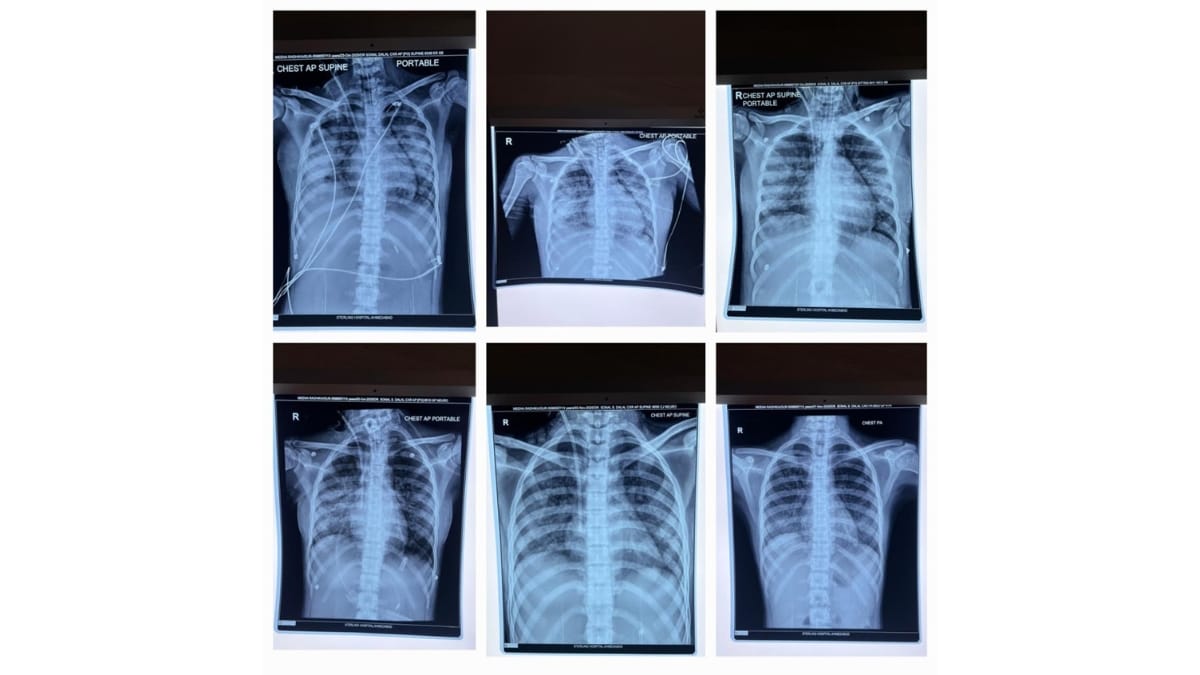

Ahmedabad (Gujarat) [India], December 10: In an inspiring example of medical excellence, doctors at Sterling Hospital, Gurukul, Ahmedabad, have saved the life of a 15-year-old girl who was battling severe Plasmodium falciparum malaria and multiple organ failure. The teenager was rushed from Rajasthan to Sterling Hospital in an extremely critical condition, struggling to breathe and dependent on ventilator support. She was diagnosed with falciparum malaria that had caused acute kidney injury, lung damage, and multi-organ complications. Under the expert care of Dr Sonal Dalal and Dr Amrish Patel (Pulmonologist & Critical Care Specialist), the ICU team initiated rapid, advanced treatment, including dialysis and specialised critical care support. She remained on a ventilator for 12 days and showed steady improvement with round-the-clock monitoring.

Sterling Hospital, Ahmedabad’s Dr Amrish Patel (Pulmonologist & Critical Care Specialist) explained that when the patient arrived, her oxygen levels were dangerously low, and she was struggling to breathe. She had been shifted from Rajasthan on ventilator support due to her fragile condition. The team immediately initiated specialised treatment to stabilise her. She was diagnosed with falciparum malaria, which had led to kidney damage, lung complications, and multi-organ involvement. After dialysis and medical management, she remained on ventilator support for 12 days, during which her life was saved through advanced care administered by the critical care team.

Dr. Amrish Patel (Pulmonologist & Critical Care Specialist) added that a bronchoscopy was performed to clear the secretions from her lungs. An essential step that further contributed to her recovery. As her condition improved, the ventilator support was gradually removed, and she was shifted to a normal room. By then, she had entered the recovery phase. After approximately 18 days of treatment, her life was saved through advanced care, and she was discharged in a stable and healthy condition.